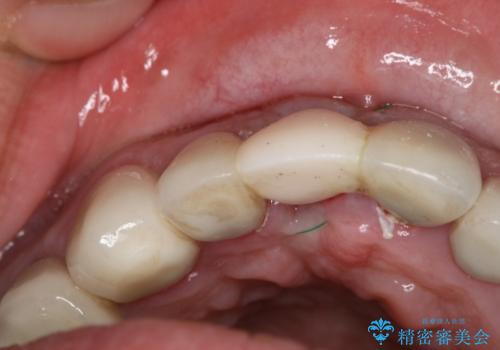

- 事故による外傷で前歯に歯根が真っ二つに折れてしまい、保存不可能となってしまった部分にインプラント治療を計画しました。

患者様のご要望もあり、審美性の確保ができる抜歯早期埋入→埋入後即時荷重という手術法を取りました。

近年、インプラントの素材や手術法の研究が進み、保存不可能となった歯牙に対して抜歯してすぐインプラントを埋入し、さらに直後から仮歯がを入れ噛むことができる【抜歯即時埋入】【即時荷重】という技法が確立されました。

従来、前歯部分のインプラントでは周囲に残っている自身の歯に仮歯を張り付けることで審美性を保ってきましたが、脱離を繰り返したり食事に耐える強度を保つのが難しいという側面がありました。

それと比較すると、今回の方法では骨にしっかりと固定されているインプラントに単独で仮歯を装着することができるためフロスも通せますし、ある程度負荷のかかる食事も気にせずできるようになります。